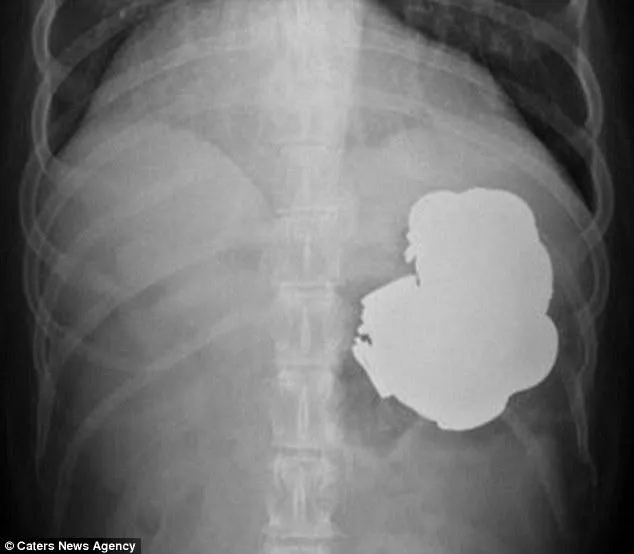

เหตุการณ์นี้เกิดที่ประเทศอินเดีย เมื่อชายคนนี้ ชื่อว่า Rajpal Singh ประกอบอาชีพชาวนา ได้ปวดท้องอย่างหนัก หลังจากไปปารตี้งานพิธีอะไรบางอย่างกับเพื่อนๆในหมู่บ้าน เเละเวลาผ่านมา2วัน เขาได้มีอาการเปิดท้องขึ้นมา นิดๆเเละเมื่อผ่านไปประมาณ หนึ่งอาทิตย์ เขาก็มีความเจ็บปวดที่รุนเเรงมากขึ้น อิก จนทนไม่ไหว ถึงกับเดินไม่ได้ หายใจไม่ค่อยออกจนพี่น้องกับญาติๆต้องพาไปที่โรงพยาบาล เเละเมื่อ ฉายรังสีเพื่อตรวจสอบกลับพบวัตถุประหลาดในท้องของเขา เเละเมื่อเเพทย์ได้ทำการผ่าตัดหน้าท้อง ถึงกับต้องอึ้งเพราะพบ วัตถุประเภทโลหะเป็นจำนวนมาก เป็นสิ่งที่ไม่นี่เกิดขึ้นในท้องของเขา เมื่อเปิดออกมาเเล้วดึงออกมาเเล้ว พบกับ เศษเหรียญ ตะปู กลอนประตู

เเบตเตอรี่สำรอง เเละเเล้วเเพทย์ก็สามารถผ่าตัดนำสิ่งเเปลกปลอมพวกนี้เเละช่วยชีวิตของเขาไว้ได้ คนในครอบครัวเผยว่าเขาเป็นคนชอบนอนละเมอหนัก ถึงขันละเมอเดินเอง ทำงาน ทำสิ่งต่างๆตอนที่หลับโดยที่เขาไม่รู้ตัว เเละนี่อาจจะเป็นสาเหตุที่ทำให้เขาอาจจะกินของพวกนี้ไปโดยไม่รู้ตัว เเละทางทีมเเพทย์ก็เห็นด้วยเพราะไม่มีเหตุผลอะไรรองรับที่จะทำให้ของพวกนี้เข้าไปอยู่ในท้องของชายคนนี้ได้เลย นอกจากการละเมอ